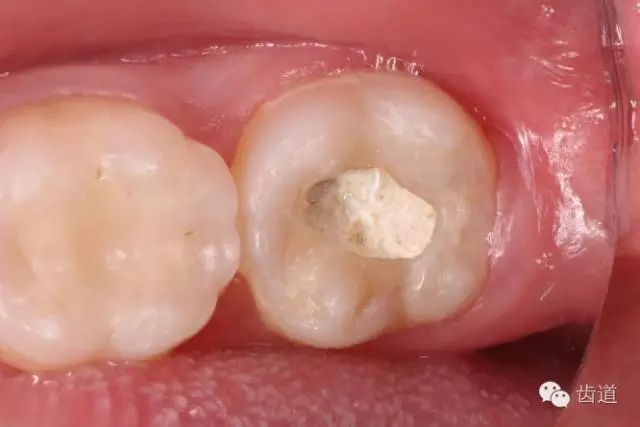

10. 術(shù)后即刻口內(nèi)照片

檢查:術(shù)后半年回訪,37牙體及合面嵌體未見缺損及裂紋,邊緣密合,未探及繼發(fā)齲,探痛-,叩痛-,松動-,冷水刺激痛-,未探及牙周袋及附著喪失,牙齦無紅腫,X線片檢查示根尖周膜連續(xù)性恢復(fù),根尖周透射影消失。

1. 術(shù)后半年口內(nèi)照片